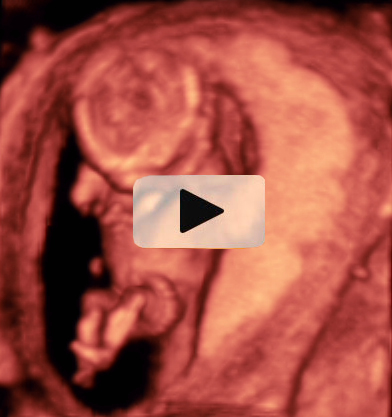

Ecografía Embarazo 4D Semana 12 - PRUEBAS DIAGNÓSTICAS